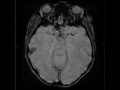

Craniopharyngioma, papillary

54-year-old female with chronic headaches and homonymous hemianopsia. There is a heterogeneous T1-hyper- and hypointense mass arising from the sella turcica and extending into the suprasellar compartment. Focal regions of central hemorrhage with more peripheral hemosiderin staining are identified. Nodular components of the lesion demonstrate diffusion restriction. The lesion abuts, elevates, and distorts the undersurface of the optic chiasm and prechiasmatic segments of the optic nerves superiorly. There is heterogeneous postcontrast enhancement. The findings are most compatible with a craniopharyngioma. Craniopharyngioma represent benign, partially cystic sellar/suprasellar lesions. 90% are cystic, have calcifications, and/or enhance. The adamantinomatous subtype are more common in children, with the papillary type more common in adults.